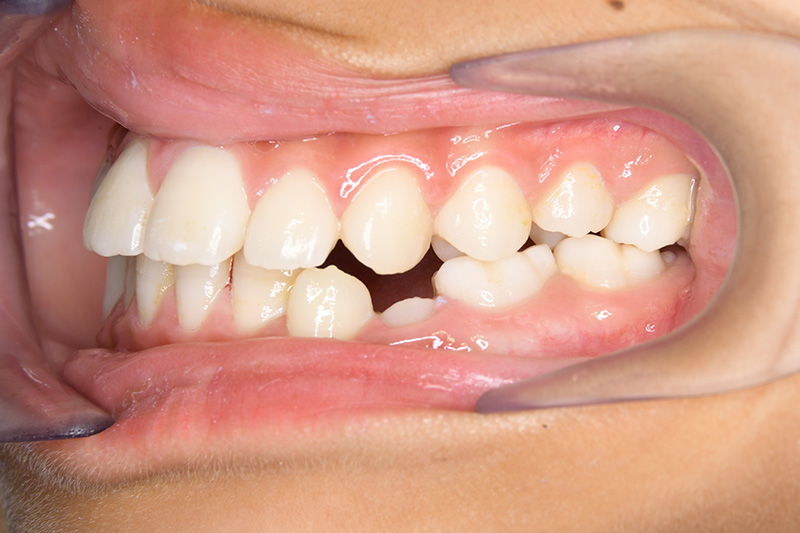

| 顔貌所見 | 正貌はほぼ左右対称。側貌はstraight type、引き締まった口唇形態をしていた。 |

| 口腔内所見 | over jet 2.5mm、over bite 2.0mm、右側大臼歯関係はEnd on class Ⅱ、上顎左側Eは早期喪失により左側大臼歯関係はFull classⅡ、右側Eは6の異所萌出により歯根吸収が進行したため一般歯科医院にて抜去済みであった。 |